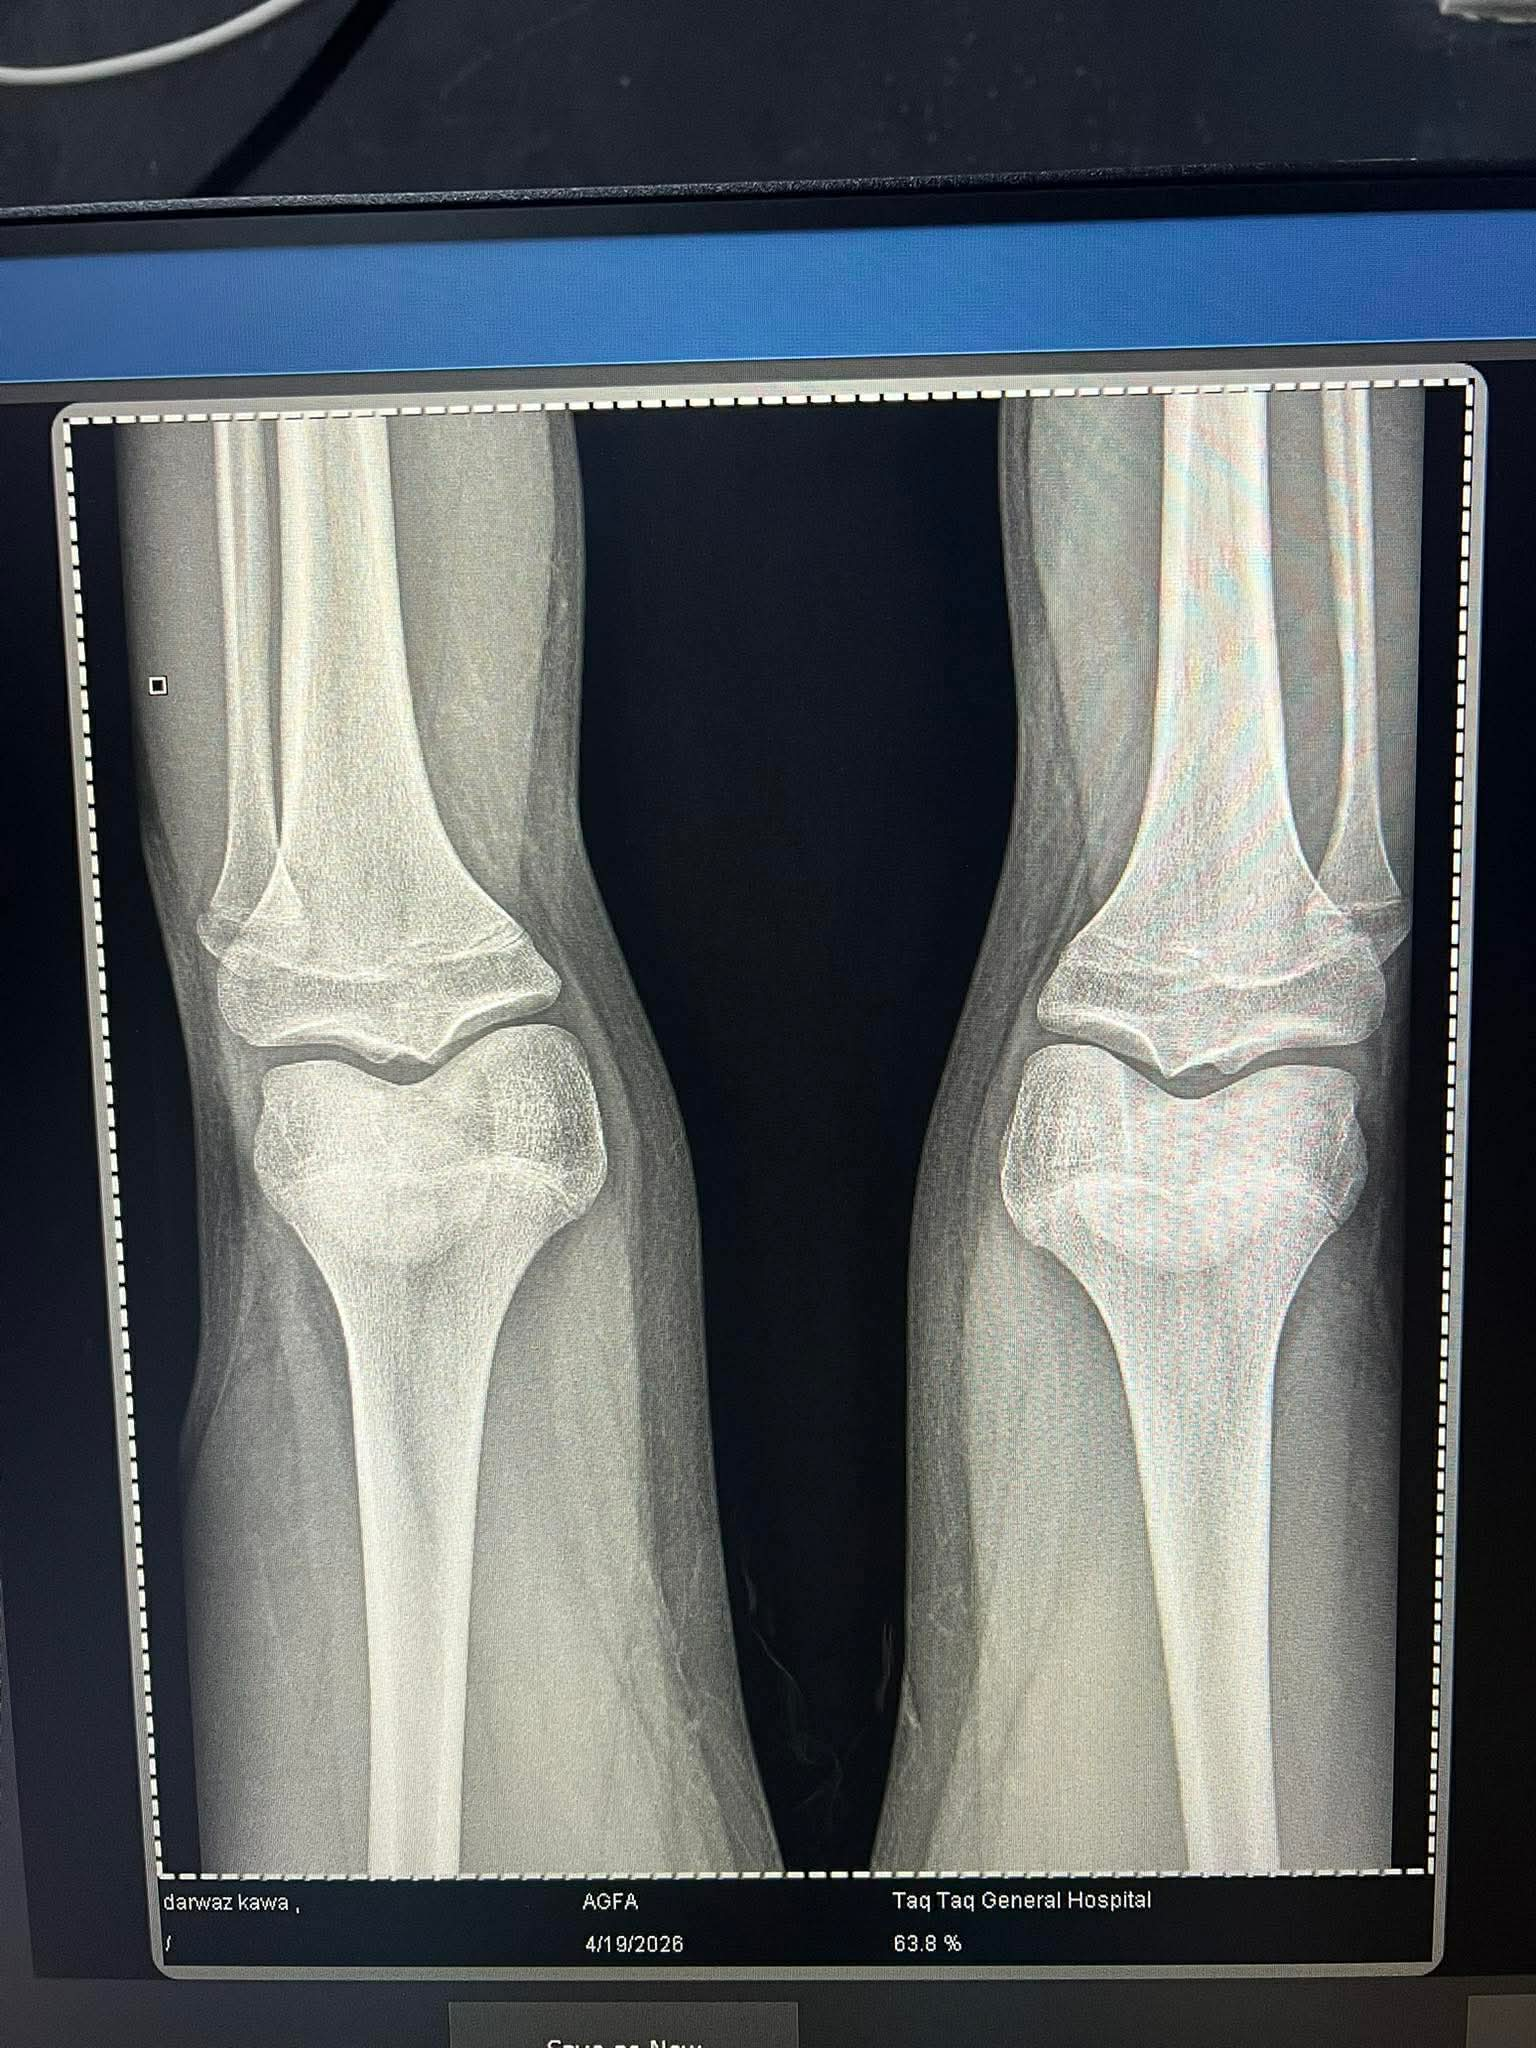

should i use aromatose inhbator my plates are slightly open??

you said in the title they are open? ff theyre fused then hgh or anything aint gonna work, if theyre slightly open get on an AI immediately to squeeze out final growth